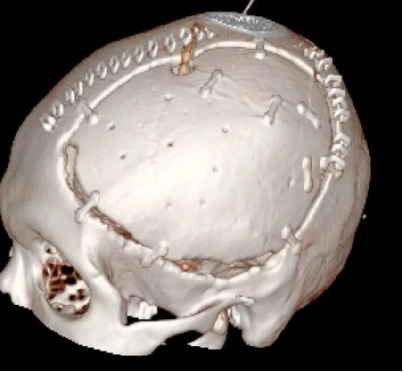

大骨瓣減壓技術常用在重症顱腦損(sǔn)傷的救治,術後常遺留有顱骨缺損。傳統(tǒng)的顱骨修(xiū)複材料雖取材方便,但存在明顯的排斥反應,而自(zì)體顱骨修補恰恰規(guī)避了這一缺點,成了(le)顱骨修複的“金標(biāo)準”。自體顱骨不存在常見的排斥反應,外形匹配、美(měi)觀,真正做到完美“顱”初。

患者術後滿三個月(yuè)再次返院進(jìn)行顱骨缺損(sǔn)修補術,經過完善術前檢查、全(quán)科討論、做好充分手術(shù)準備後,武(wǔ)寧縣總醫院人民醫院院區神(shén)經外科團隊成功為患者完成(chéng)自體顱骨修補術(shù)。

術後: